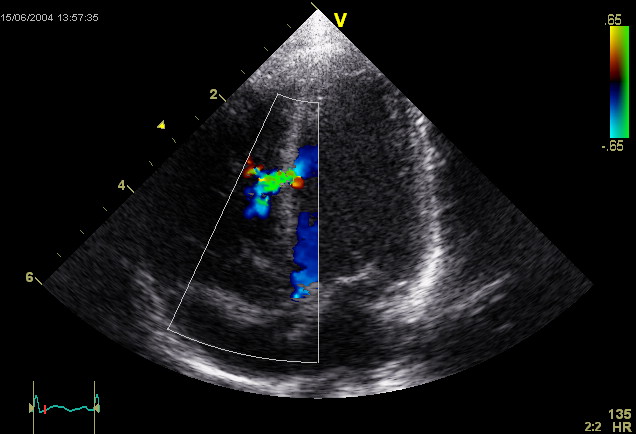

Ventricular Septal Defect (VSD)

A ventricular septal defect is a flaw in the wall that separates the right and left ventricles, or septum.

Ventricular septal defect is the most common congenital cardiac condition.

Ventricular septal defect is inextricably linked to fetal alcohol syndrome.

Ventricular septal defect results in a shunt from left to right.

Age at presentation and defect size both depend on the ventricular septal defect size.

Large ventricular septal defect can cause Eisenmenger syndrome.

Treatment of large ventricular septal defect involves surgery.

Small ventricular septal defects are frequently asymptomatic.

Small flaws might naturally close.